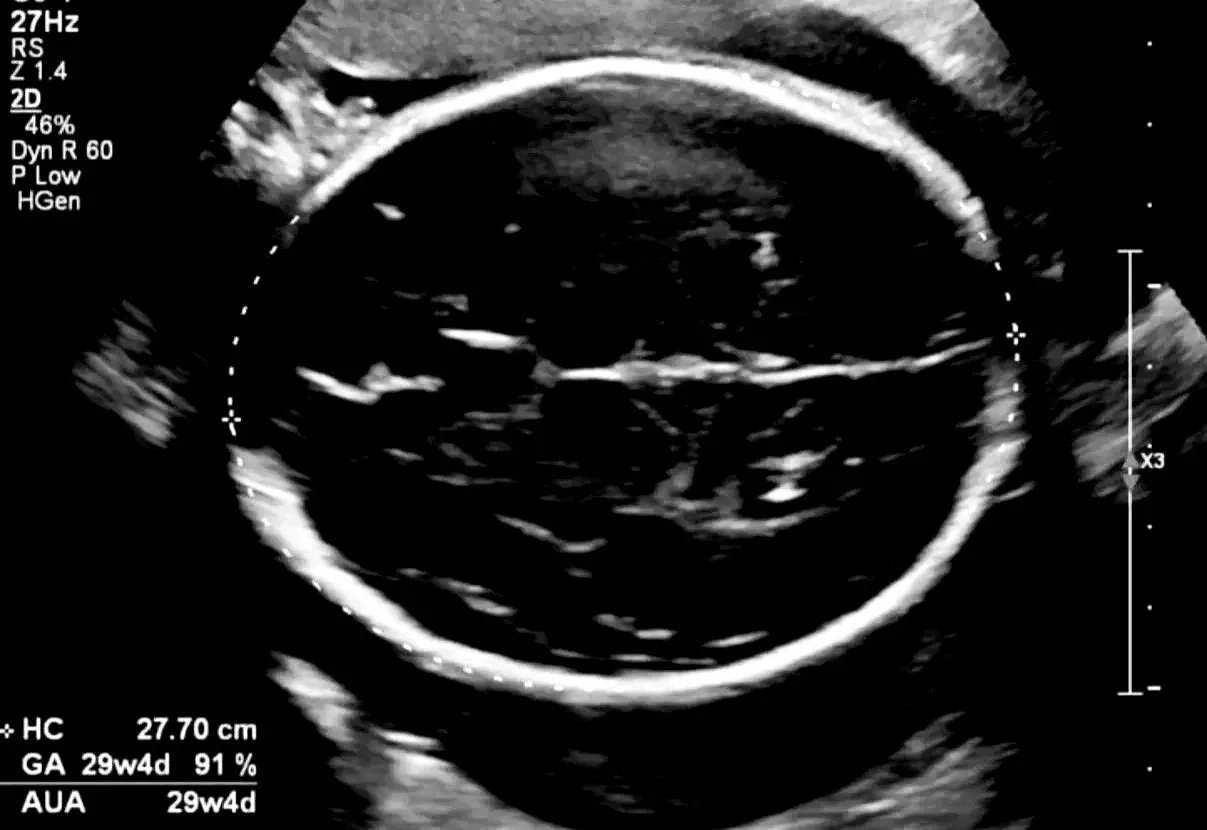

Groeiecho

Soms is het nodig om extra echo’s te maken, bijvoorbeeld als je buik sneller of juist minder snel groeit, bij twijfel over de ligging van de baby of als er medische redenen zijn voor extra controle.

Met een groeiecho meten we onder andere het hoofdje, buikje en dijbeen van je baby en kijken we naar de hoeveelheid vruchtwater.